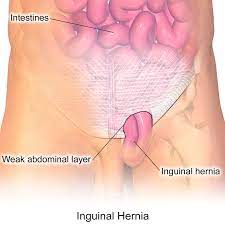

Overview

Package includes:

Days in hospital : 3 to 4 Days (For patient and one attendant)

Days in hotel : 15 Days (For patient and one attendant)

Room type in hospital : Shared

Room type in hotel : Private

Hotel category: Standard

Value added benefits of the Herniorrhaphy - Inguinal - Unilateral:

Ø Doctor consultation charges

Ø Lab tests and diagnostic charges

Ø Room charges inside hospital during the procedure

Ø Surgeon Fee

Ø Nursing charges

Ø Hospital surgery suite charges

Ø Anesthesia charges

Ø Routine medicines and routine consumables (bandages, dressings etc.)

Ø Food and Beverages inside hospital stay for patient and one attendant.

Extra benefits:

ü Interpreter

ü Visa assistance

Ø Site tourism of the city

Ø Follow up with the doctor

Ø Airport pick up and drop

Ø Free online consultation with the doctor

Ø Priority appointments with the doctor

Ø Room upgrade from sharing to private

Overview

Package includes:

Days in hospital : 3 to 4 Days (For patient and one attendant)

Days in hotel : 15 Days (For patient and one attendant)

Room type in hospital : Shared

Room type in hotel : Private

Hotel category: Standard

Value added benefits of the Hernioplasty Inguinal with Mesh:

Ø Doctor consultation charges

Ø Lab tests and diagnostic charges

Ø Room charges inside hospital during the procedure

Ø Surgeon Fee

Ø Nursing charges

Ø Hospital surgery suite charges

Ø Anesthesia charges

Ø Routine medicines and routine consumables (bandages, dressings etc.)

Ø Food and Beverages inside hospital stay for patient and one attendant.

Extra benefits:

ü Interpreter

ü Visa assistance

Ø Site tourism of the city

Ø Follow up with the doctor

Ø Airport pick up and drop

Ø Free online consultation with the doctor

Ø Priority appointments with the doctor

Ø Room upgrade from sharing to private

Overview

Package includes:

Days in hospital : 2 to 3 Days (For patient and one attendant)

Days in hotel : 15 Days (For patient and one attendant)

Room type in hospital : Shared

Room type in hotel : Private

Hotel category: Standard

Value added benefits of the Hernioplasty Inguinal Bilateral with mesh:

Ø Doctor consultation charges

Ø Lab tests and diagnostic charges

Ø Room charges inside hospital during the procedure

Ø Surgeon Fee

Ø Nursing charges

Ø Hospital surgery suite charges

Ø Anesthesia charges

Ø Routine medicines and routine consumables (bandages, dressings etc.)

Ø Food and Beverages inside hospital stay for patient and one attendant.

Extra benefits:

ü Interpreter

ü Visa assistance

Ø Site tourism of the city

Ø Follow up with the doctor

Ø Airport pick up and drop

Ø Free online consultation with the doctor

Ø Priority appointments with the doctor

Ø Room upgrade from sharing to private